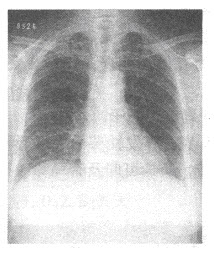

B.舟距关节

女性,46岁。呼吸困难入院。胸部X线平片如下图。右侧肋膈角区垂直于胸壁内侧面的线状影为()

A.KerleyA线

B.KerleyB线

C.KerleyC线

D.盘状肺不张

E.胸腔积液